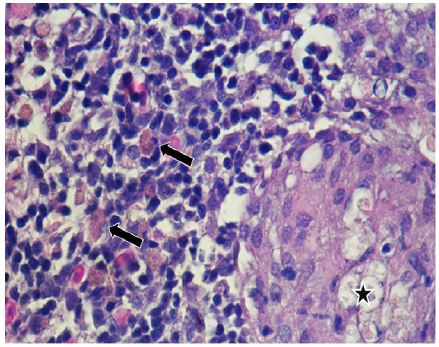

Histopathology. To the histopathological reading of the 16 tilapia positive presumed to S. iniae was observed:

Spleen: In 12.5% (2/16) of the cuts, the perisplenic area was observed thickened with the presence of inflammatory exudate composed of neutrophils and macrophages on condensed fibrin, and in some cases, the presence of fibroblasts; compatible with a fibrin-suppurative acute or chronic type perisplenitis (Figure 2-a). In 50% (8/16) bacterial nests and areas of necrosis were noted. In addition, other cuts congestion showed 68.75% (11/16) in the depletion 18.75% and increased melanomacrophages centres in 43.75% (7/16).

In 12.5% (2/16) of the cuts granulomas, composed by aggregated macrophages which were circumscribed by fibroblasts. Also, the hepatopancreas showed an inflammatory exudate (Figure 3-4) it was evidenced. Moreover, 75% (12/16) of sample fish showed necrosis. While in 56.25% (9/16) steatosis and hydropic degeneration of hepatocytes was evidenced.

Figure 3 Histopathological findings in Oreochromis niloticus. Photomicrograph of the hepatopancreas showing a granulome with aggregated macrophages (star) and free melanomacrophages (arrows). Hematoxilin-Eosine, Scale bar = 20 µm.